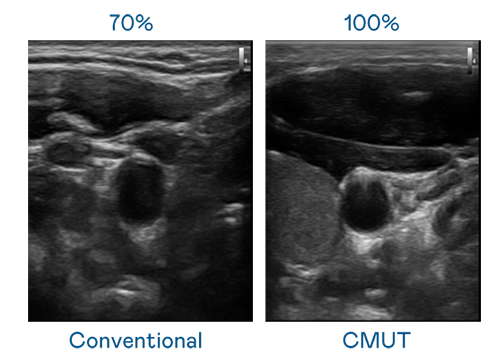

CMUT 技术是一种用电容式微机电元件来产生超音波讯号的技术。与传统 PZT 压电式技术相比,CMUT 频宽增加 30%,更宽频的超音波讯号让影像解析度大幅提升,是实现高影像品质医疗超音波扫描、促进精准医疗发展的关键技术。

大频宽带来超清晰影像

超音波影像的解析度高低,首先取决于探头能发出的讯号频宽。尊龙凯龙时官网进入 CMUT 可提供高清晰的超音波讯号,提供高频宽、高灵敏度、影像纹理细节更高的超音波影像,协助医护人员缩短影像判读时间及利用精准的医疗影像进行诊断。